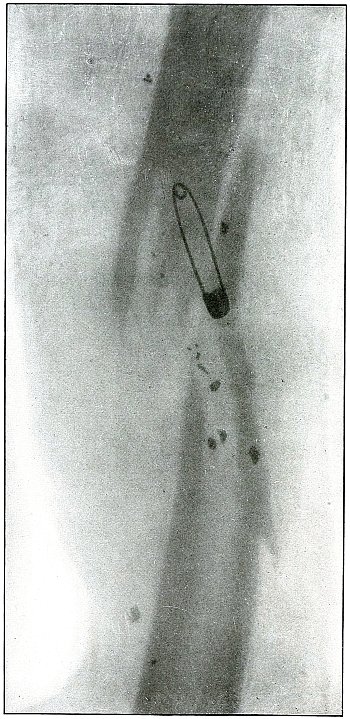

Plate 49.

[Pg 109]

Rifle—Plate 49.

LOWER EXTREMITY.

Gunshot Wound of the Right Thigh,

with Lodgment of the Bullet Behind the Femur.

There is no injury of the bone in this case, as the bullet lodged in

the muscles posterior to the lower third of the femur without striking

the bone. The lighter circular area of the larger end of the shadow

of the projectile shows that its base is farther from the plate than

its nose, which was probably flattened and bent by the ricochet which

reduced its velocity so as to give it but slight power of penetration.

It is not easy to determine from inspection of the plate which side of

the leg lay next to the plate.

With a history of the wound of the right thigh and with the outside

of the leg next to the plate, the projectile must have lain near the

plate on the outside behind the lower end of the femur, midway between

the skin and bone.

The markings seen on the bone are not concerned with the wound, as the

same effect in the plate is seen in the areas beside the bone.

The treatment is conservative; infection is rare.